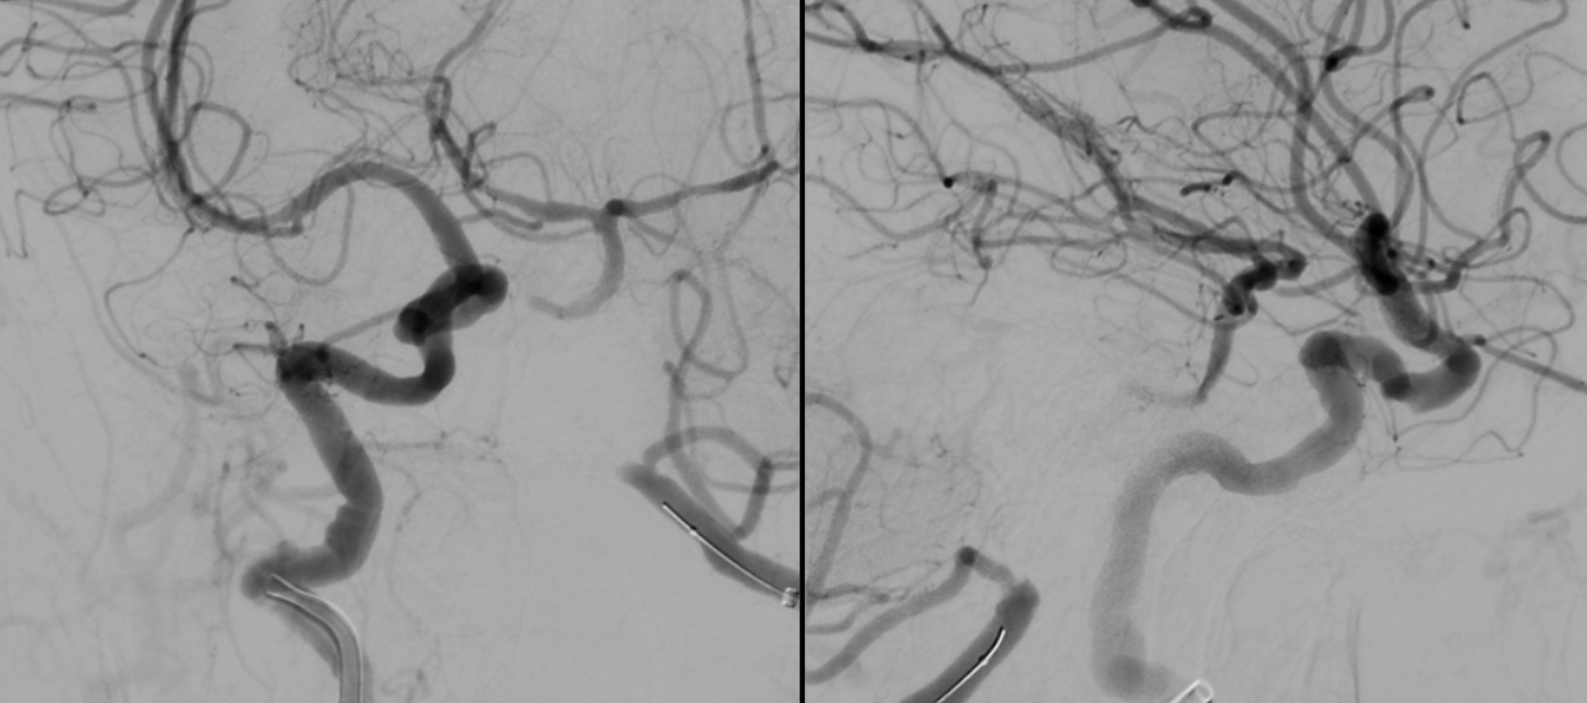

Once you are through, follow the wire with microcatheter, replace wire with snare, catch the wire coming up from below, and bring it up through the stenosis… sounds easy, huh…

Now, image through a microcatheter from below

Stenting. Lots of calcs